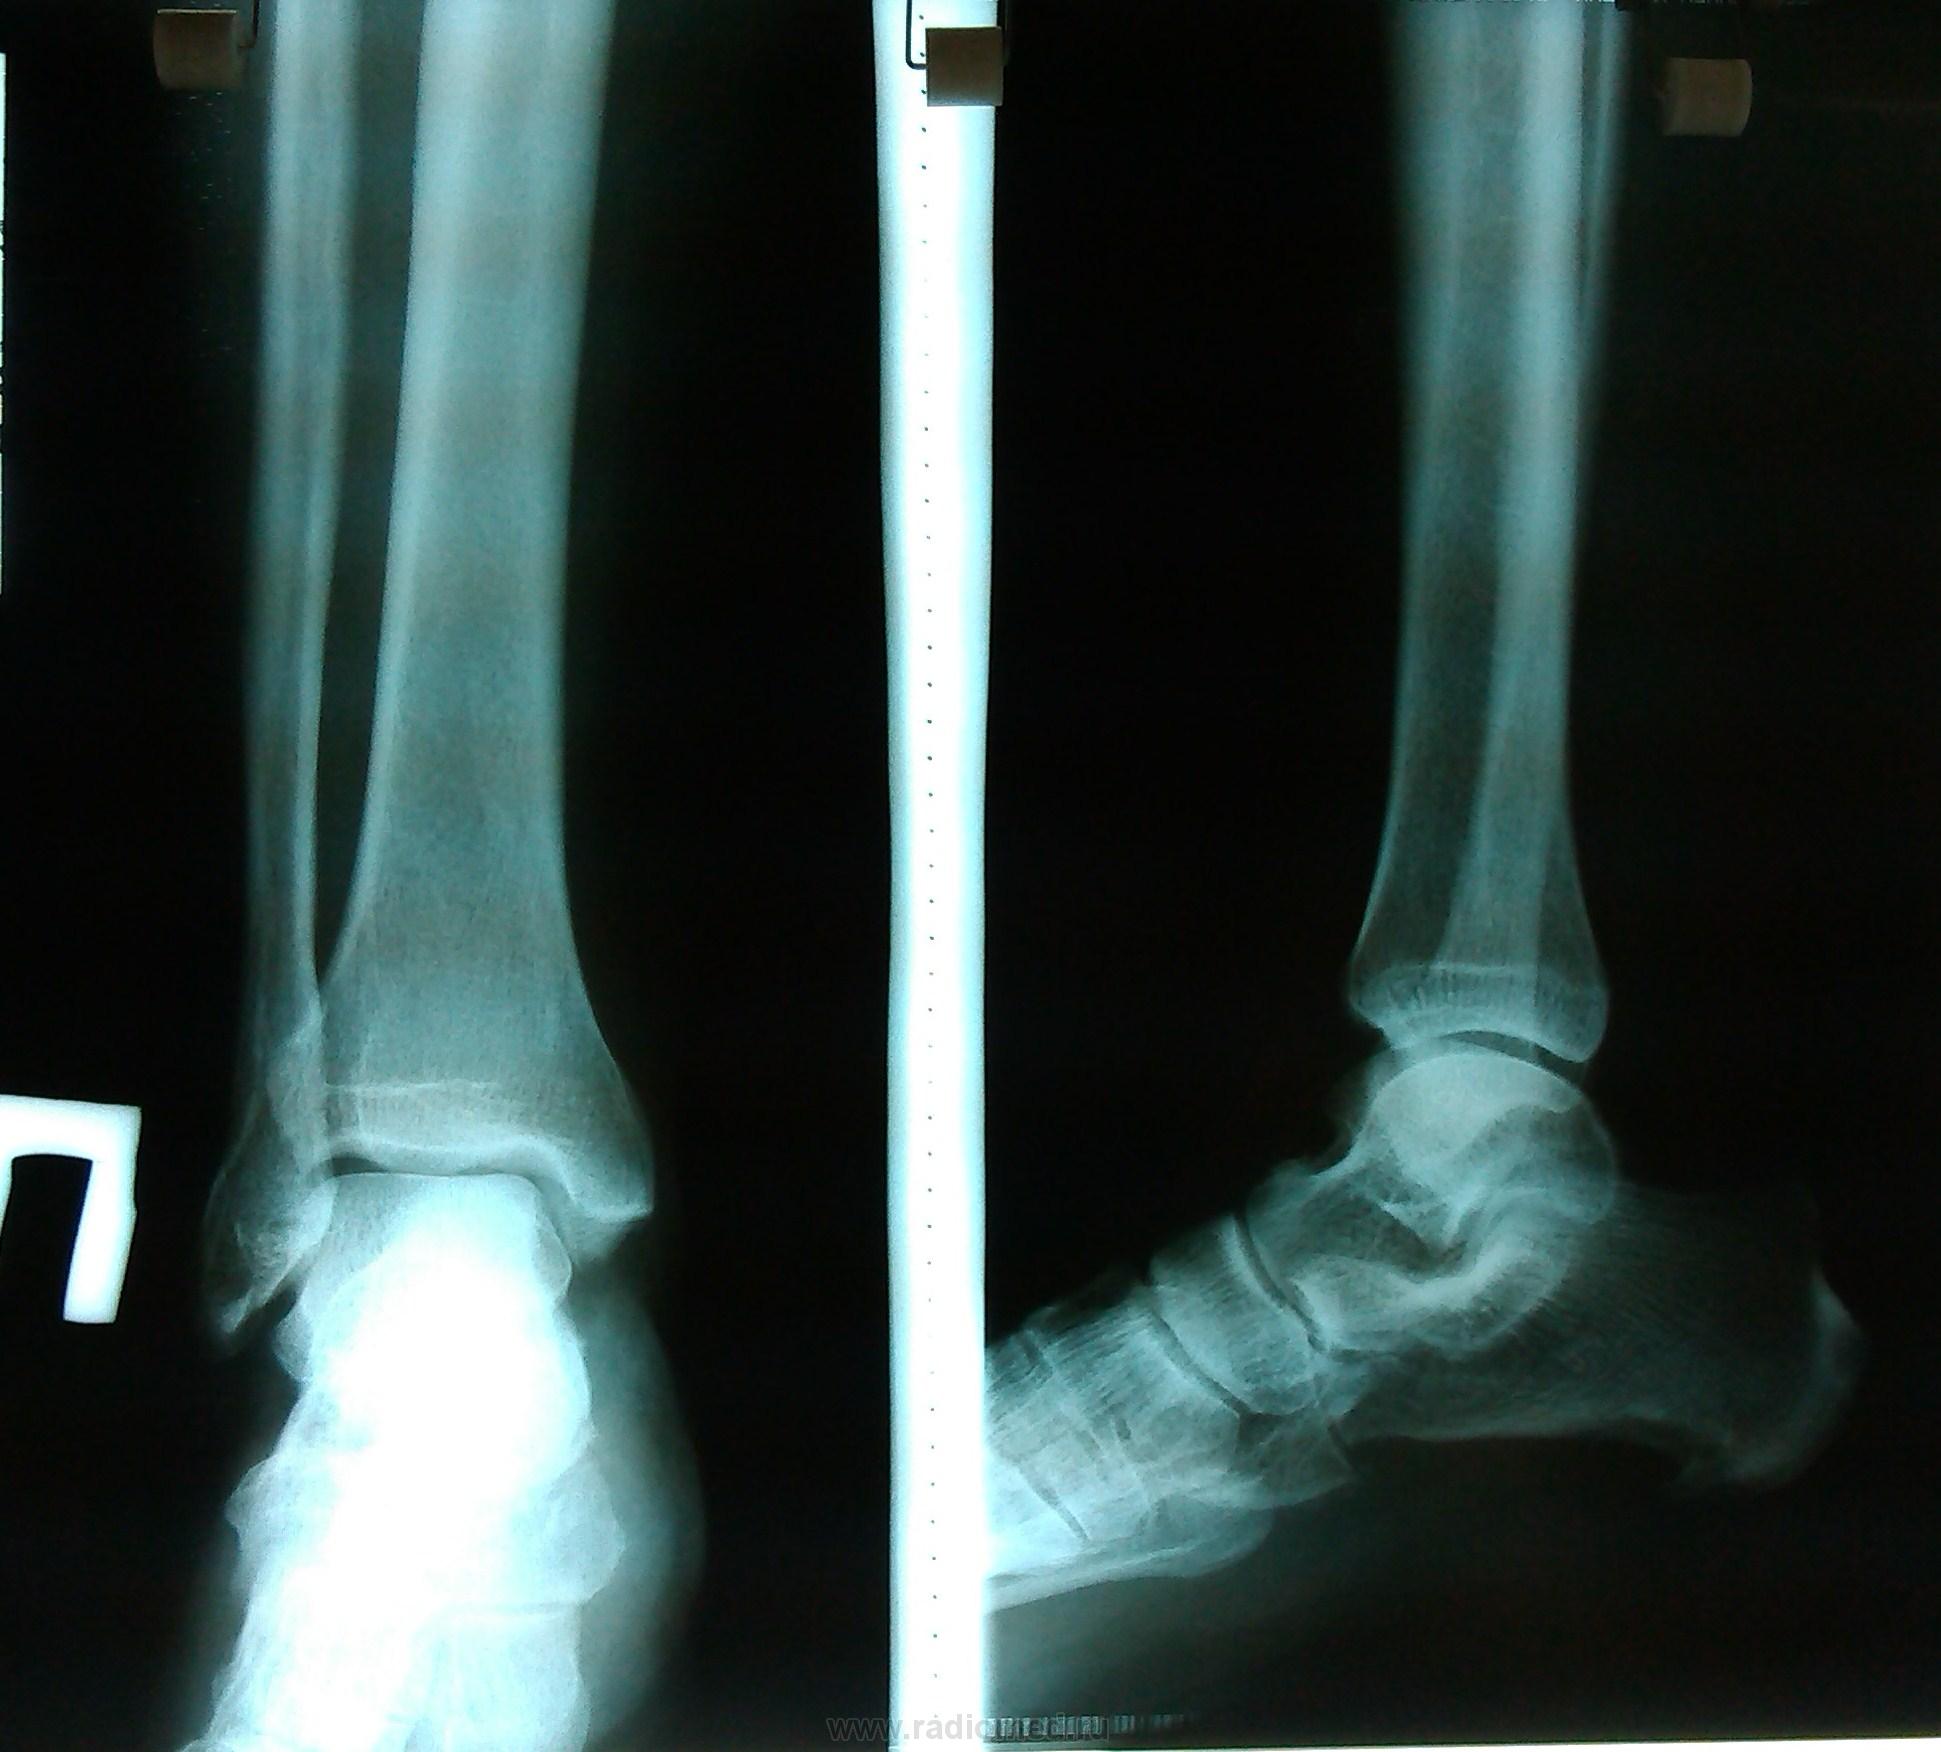

Пол пациента: Женский пол Тип патологии: Другое Область исследования: Скелетно-мышечная система Методы исследования: Rg Пациентка , 49 лет. Ds: Остеоартроз обоих голеност-х суставов. Дополнительная тень левой большеберцовой кости? https://radiomed.ru/sites/default/files/styles/case_slider_image/public/user/18609/img_20130813_160611.jpg?itok=MJd9oCoL ID:30750 Втр, 13/08/2013 - 22:20 #1 Андрей Юрьевич Не на сайте Был на сайте: 6 дней 20 часов назад Зарегистрирован: 16.11.2008 - 22:16 Публикации: 18098 Сосуд, по всей видимости. Андрей Юрьевич Ср, 14/08/2013 - 11:56 #2 Алексей Игореви... Не на сайте Был на сайте: 6 лет 10 месяцев назад Зарегистрирован: 08.08.2012 - 21:52 Публикации: 786 Ну так она не в кости. Или сосуд, или какой-то кальцинат в мягких тканях. "Обучая других - учишься сам". Н.И.Пирогов Ср, 14/08/2013 - 12:40 #3 stovbav Не на сайте Был на сайте: 2 года 2 месяцев назад Зарегистрирован: 20.12.2009 - 17:28 Публикации: 7066 Гетеротопическое окостенение в параоссальных тканях. Генез - как правило постравматического характера, но не факт. Болезни ног: виды, симптомы, причины, профилактика и лечение

Гетеротопическое окостенение в параоссальных тканях.

Генез - как правило постравматического характера, но не факт.